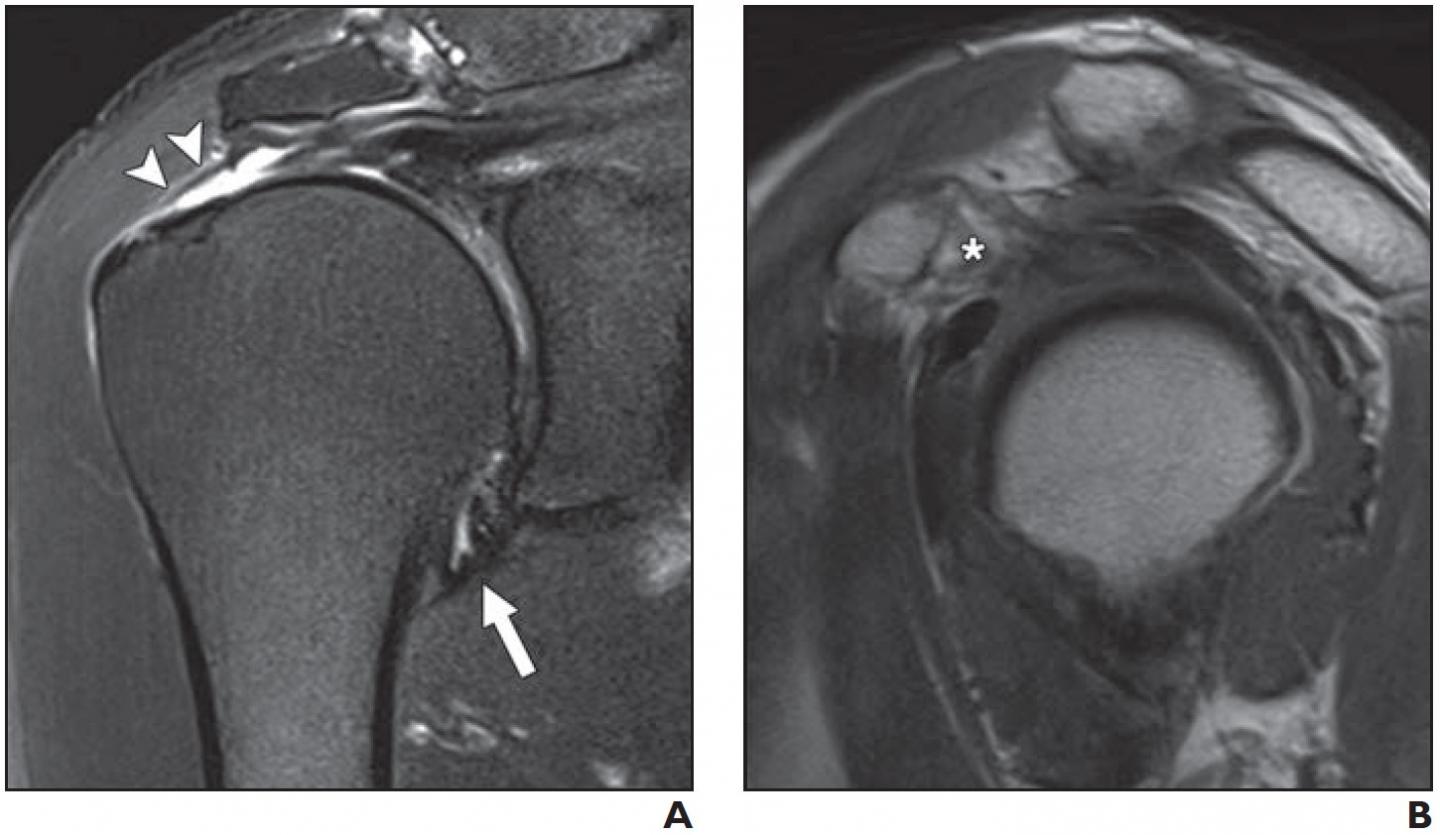

image: A: Oblique coronal fat-suppressed T2-weighted MR image shows normal hypointense joint capsule at axillary recess (arrow). Note full-thickness tear of supraspinatus tendon (arrowheads)

B: Oblique sagittal proton density MR image shows preserved subcoracoid fat triangle (asterisk)